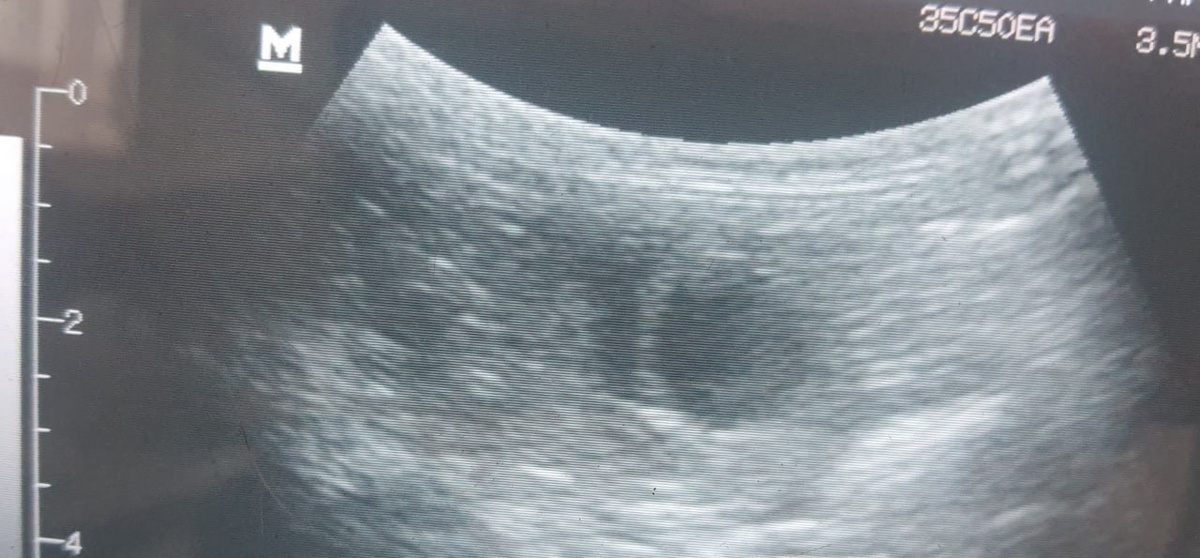

Кисты в почках. Доброкачественное, заполненное жидкостью, образование в ткани почки. Они могут быть одиночными (солитарными) — чаще возрастные изменения, слабо влияющие на функцию почек. Может быть и поликистоз почек (ПКП) — наследственное заболевание, чаще характерное для персидских, экзотических, британских и шотландских пород. При ПКП со временем образуется множество кист в обеих почках, которые постепенно замещают здоровую ткань, приводя к почечной недостаточности. Мероприятия следующие.

Общий анализ мочи с микроскопией осадка: удельный вес (плотность) мочи — ключевой показатель концентрационной способности почек. Наличие белка, кристаллов, инфекции. Если киста одиночная, маленькая (например, <1 см), анализы крови и мочи в норме, кот молод и симптомов нет, то тактика - наблюдение. Повторить УЗИ почек и анализы крови/мочи через 6-12 месяцев для контроля динамики. Если киста не растет и функция не страдает, далее контроль раз в 1-2 года.